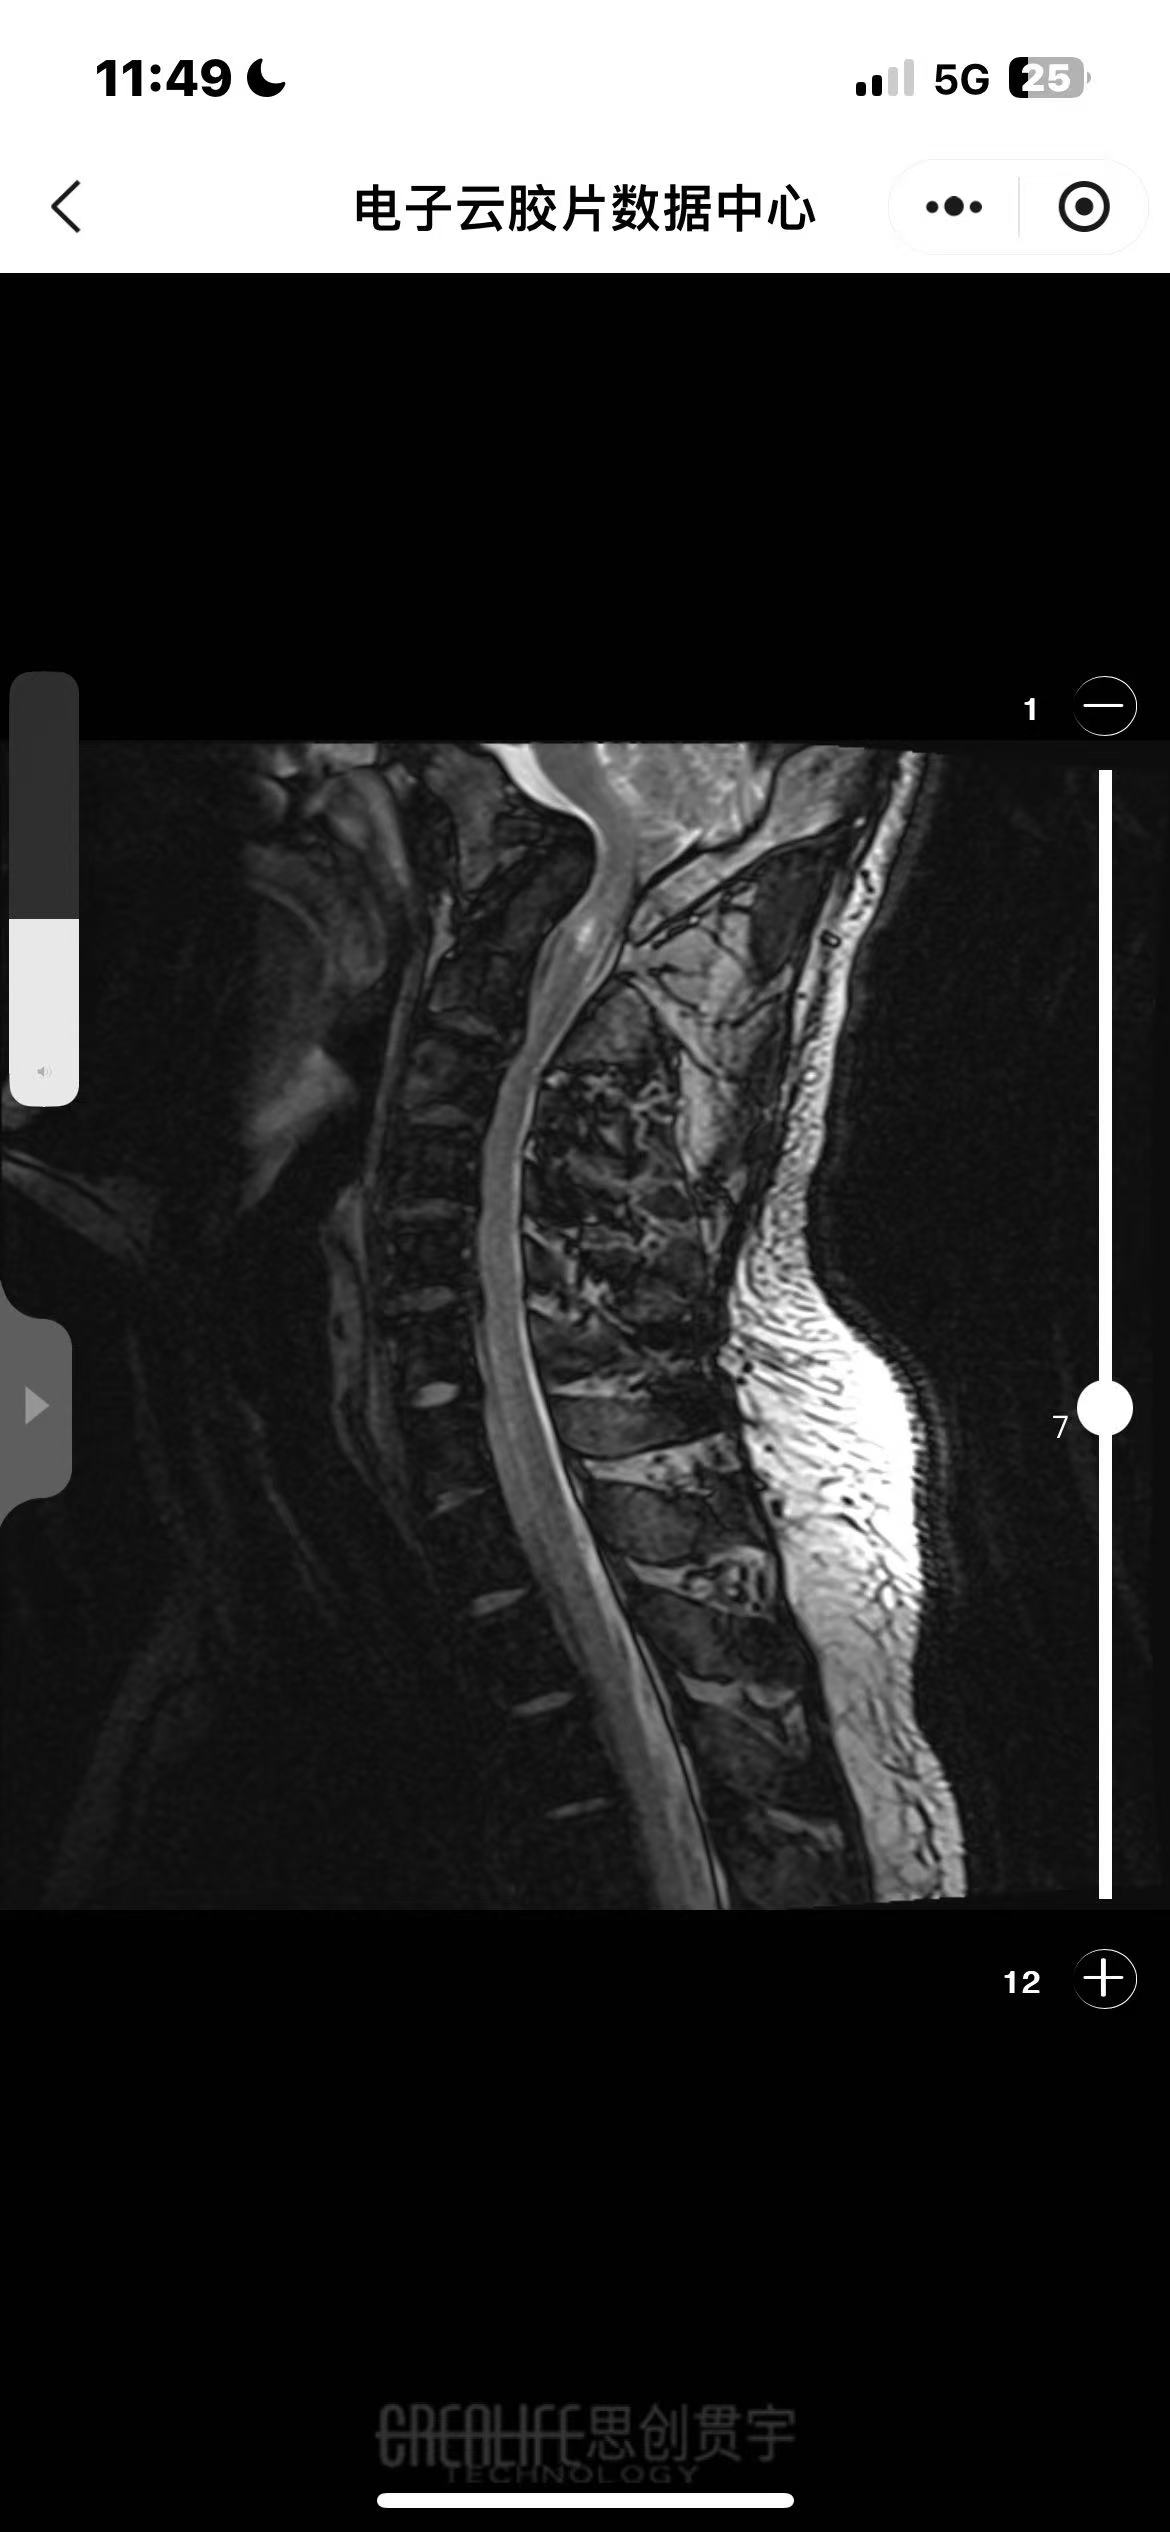

• 诊断:寰枢椎脱位、颅底凹陷

• 影像:

• 术后状况:属于难复位型的,采取后路松解,且用了融合器